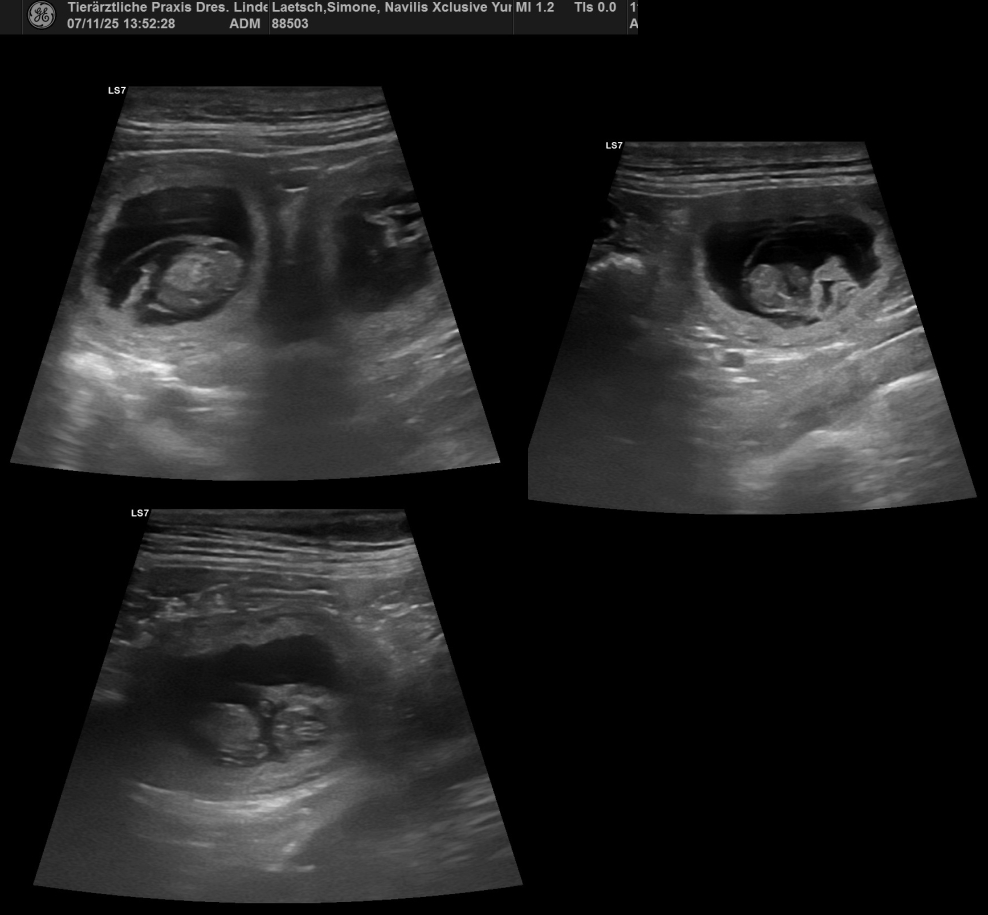

Am 28. Trächtigkeitstag war es dann endlich so weit.

Wir haben eine Menge kleiner

Kind of Magics gesehen!!!!!!!! *freu!!*

Auch wenn ich mir schon im Vorfeld zu 99 Prozent sicher war,

dass Yuma Babys erwartet, verzichte ich nicht auf den Ultraschall.

Yuma macht das ganz easy, hat keine Angst davor, und ich

kann mir relativ sicher sein, dass es nicht nur 1, 2 oder 3 Babys sind,

was eher zu Komplikationen bei der Geburt führen kann,

als wenn eine "normale" Wurfgröße zu erwarten ist....